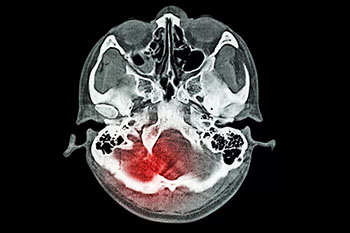

小品艺术家赵本山,09年在片场突然出现先剧烈头痛伴恶心呕吐不适,后内诊断为“蛛网膜下腔出血”,脑血管造影证实为“颅内动脉瘤”,之后接受了动脉瘤介入治疗,后康复出院,并重返舞台。

蛛网膜下腔出血是出血性脑血管病的一种,这种疾病和普通的脑出血是不一样的,普通的脑出血一般都是指脑实质内出血,而蛛网膜下腔出血,它是由于脑子里面出血,年轻患者蛛网膜下腔出血大多数都是因为颅内动脉瘤或者脑血管畸形,而老年人患这种疾病一般为动脉瘤脑动脉硬化,这种疾病的病情变化非常快,病情很危重,所以一旦出现头痛的话,可能就会对患者出现昏迷等各种的不良反应影响,严重的话,可能会危及生命。

蛛网膜下腔出血是一种症状表现,由于多种原因引起的脑血管突然破裂,是血液进入颅内或椎管内的蛛网膜下腔所引起的综合征。临床上将蛛网膜下腔出血分为自发性和外伤性两类。

蛛网膜下腔出血的治疗是一项综合治疗,目的是为了防止再出血、血管痉挛及脑积水等并发症,降低死亡率和致残率。在确诊之后,应尽早进行脑血管造影或CT血管成像检查,一旦正式为颅内动脉瘤破裂,尽快准备实施开颅夹闭手术或血管内介入栓塞治疗。